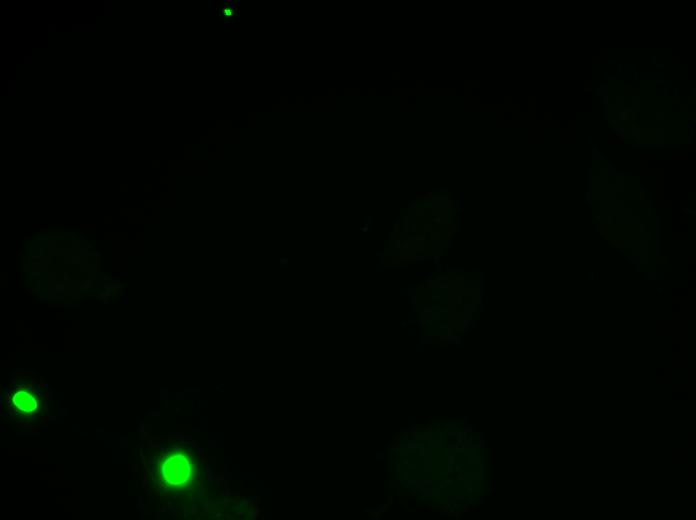

Overlay